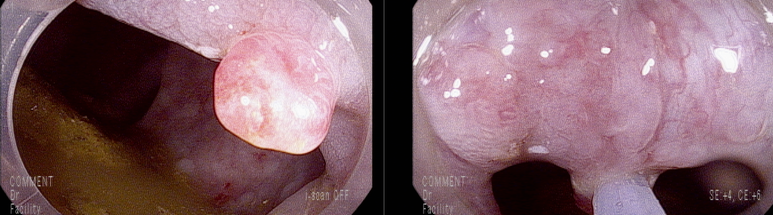

두번에 걸쳐 용종 절제술 시행함

조직 결과; Hyperplastic polyp (과증식 용종) with erosion and regenerative atypia